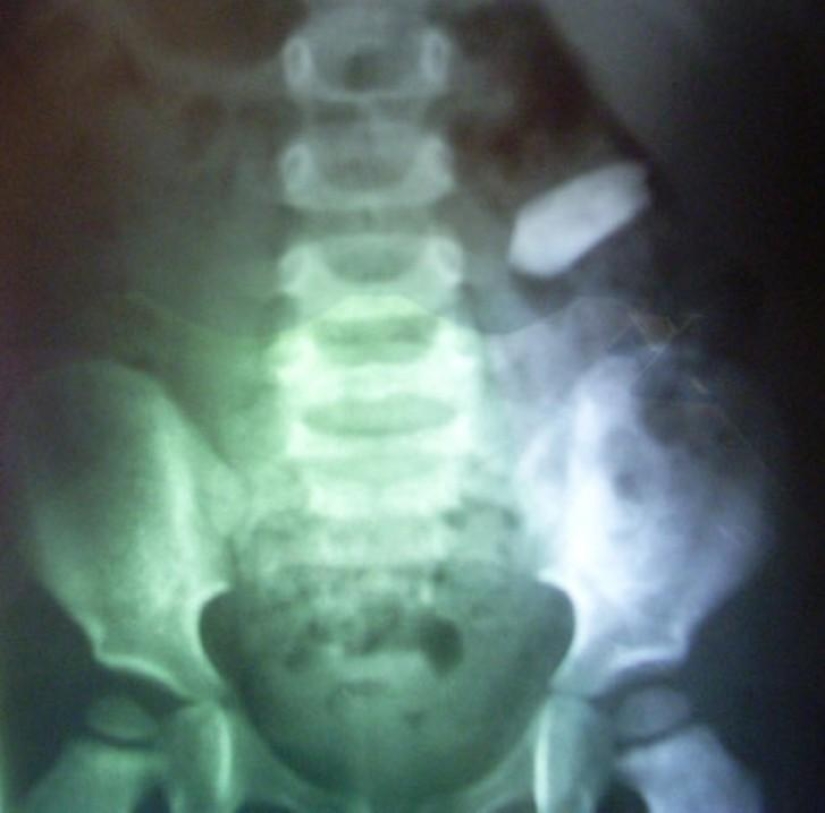

2. Bala.